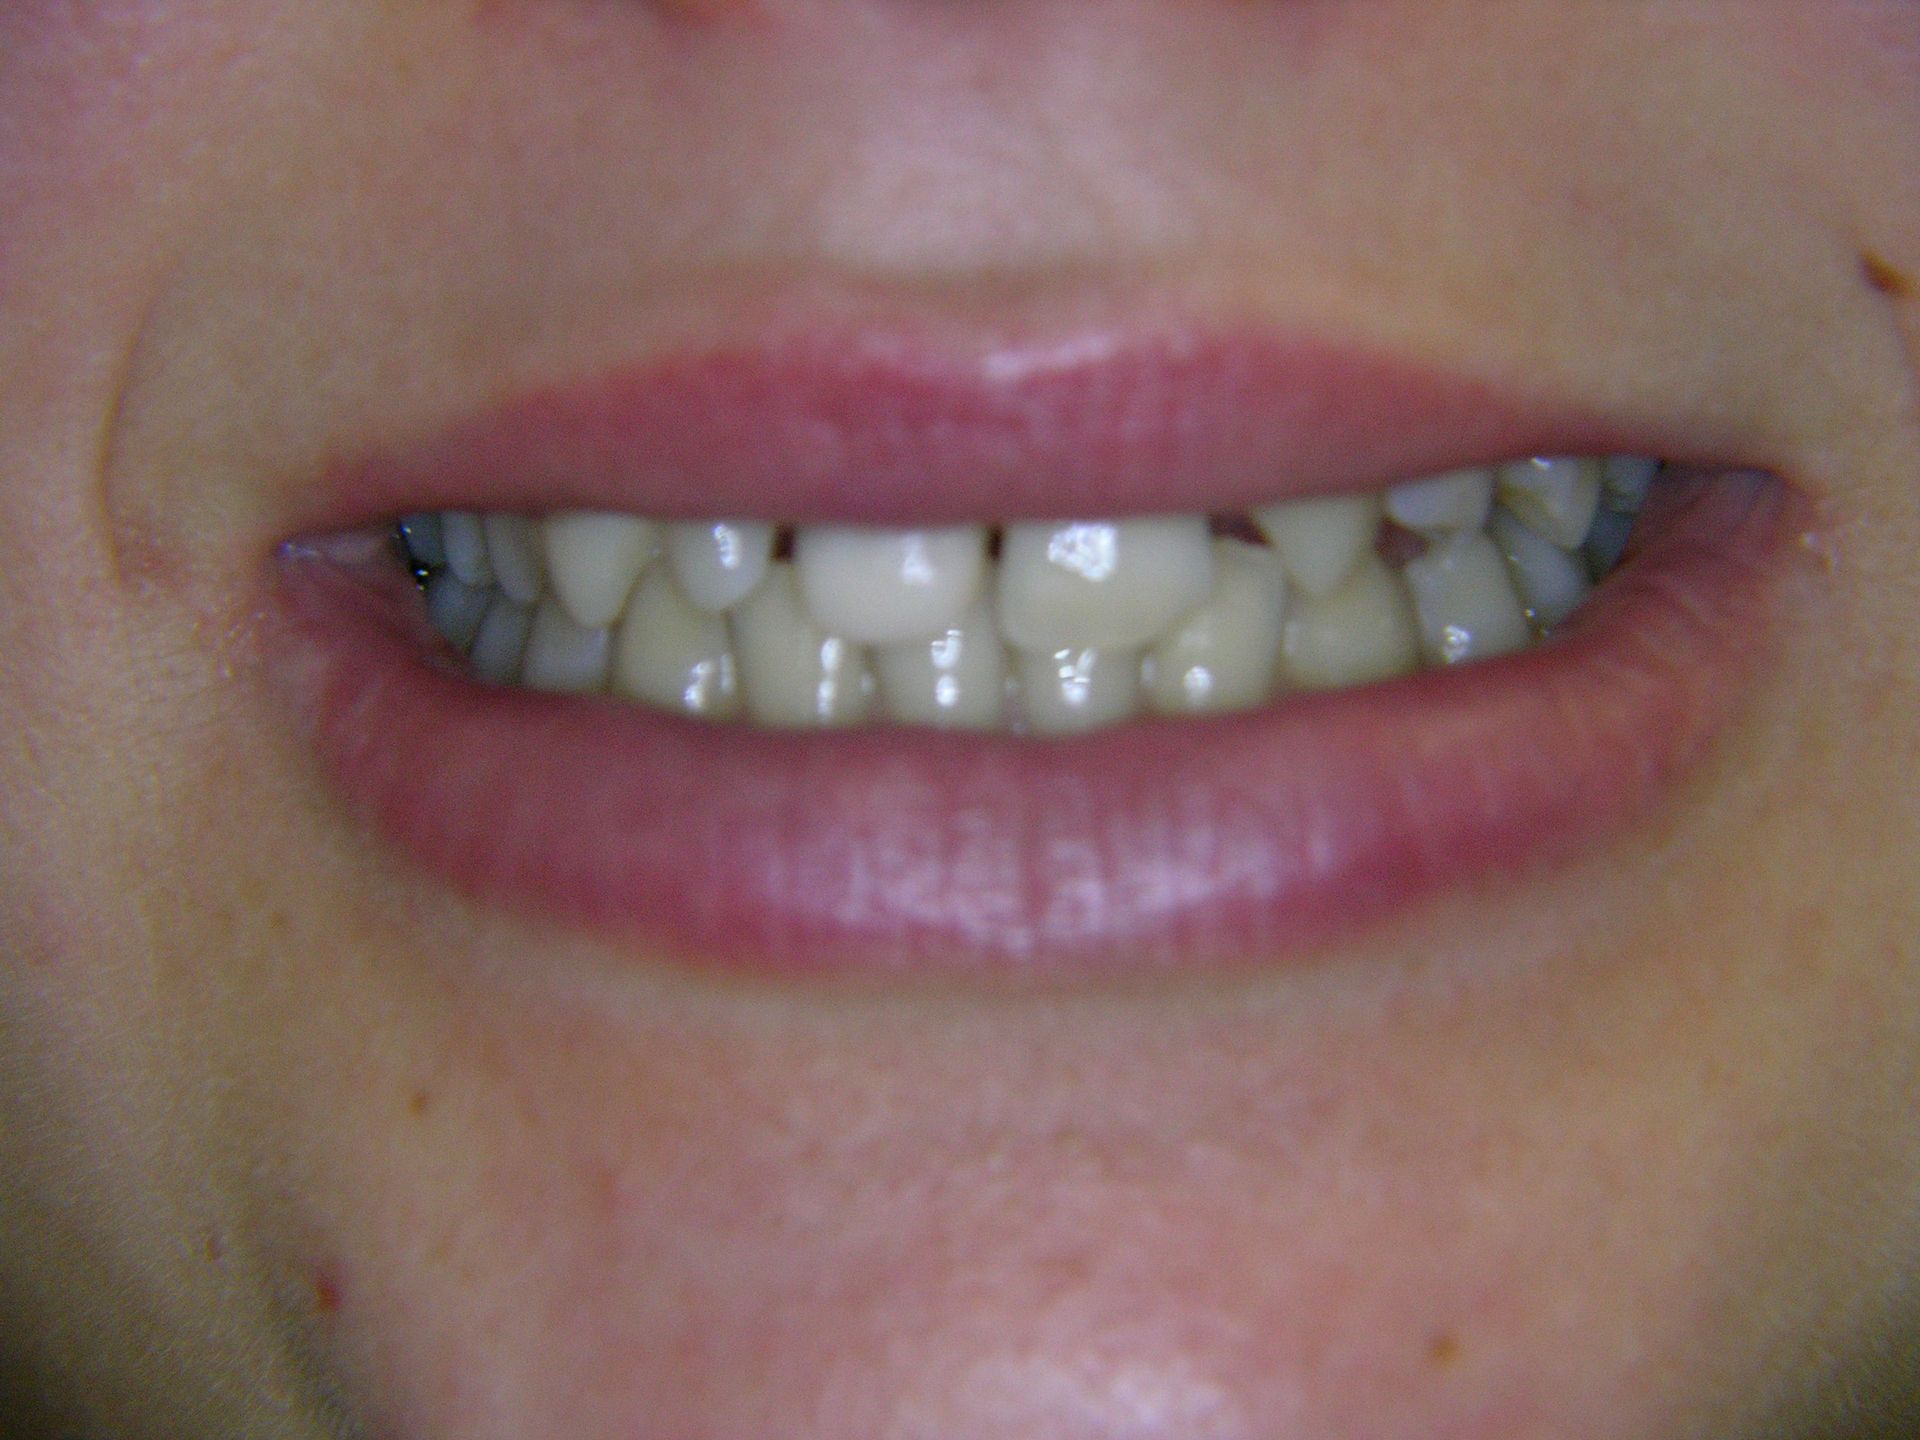

Beispiele von Versorgungen